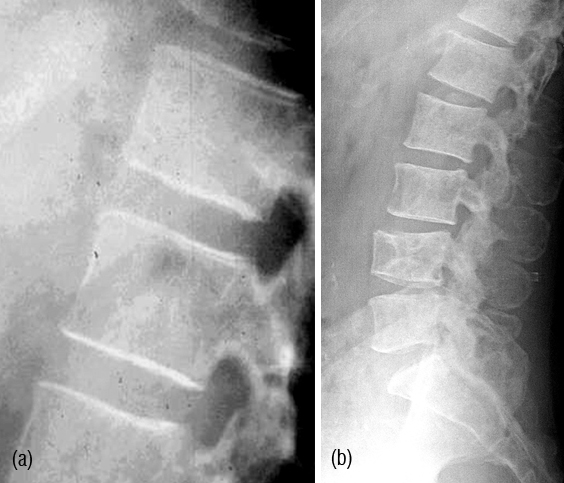

Figure 6: Multiple Myeloma – (a) Diffuse osteopenia with loss of trabeculae, (b) lytic lesions in the bodies.

Figure 7: (a,b,c) Multiple myeloma with osteopenia and early collapse of vertebral bodies BC MRI of the same patient. (d) plain films, (e, f) MRI.